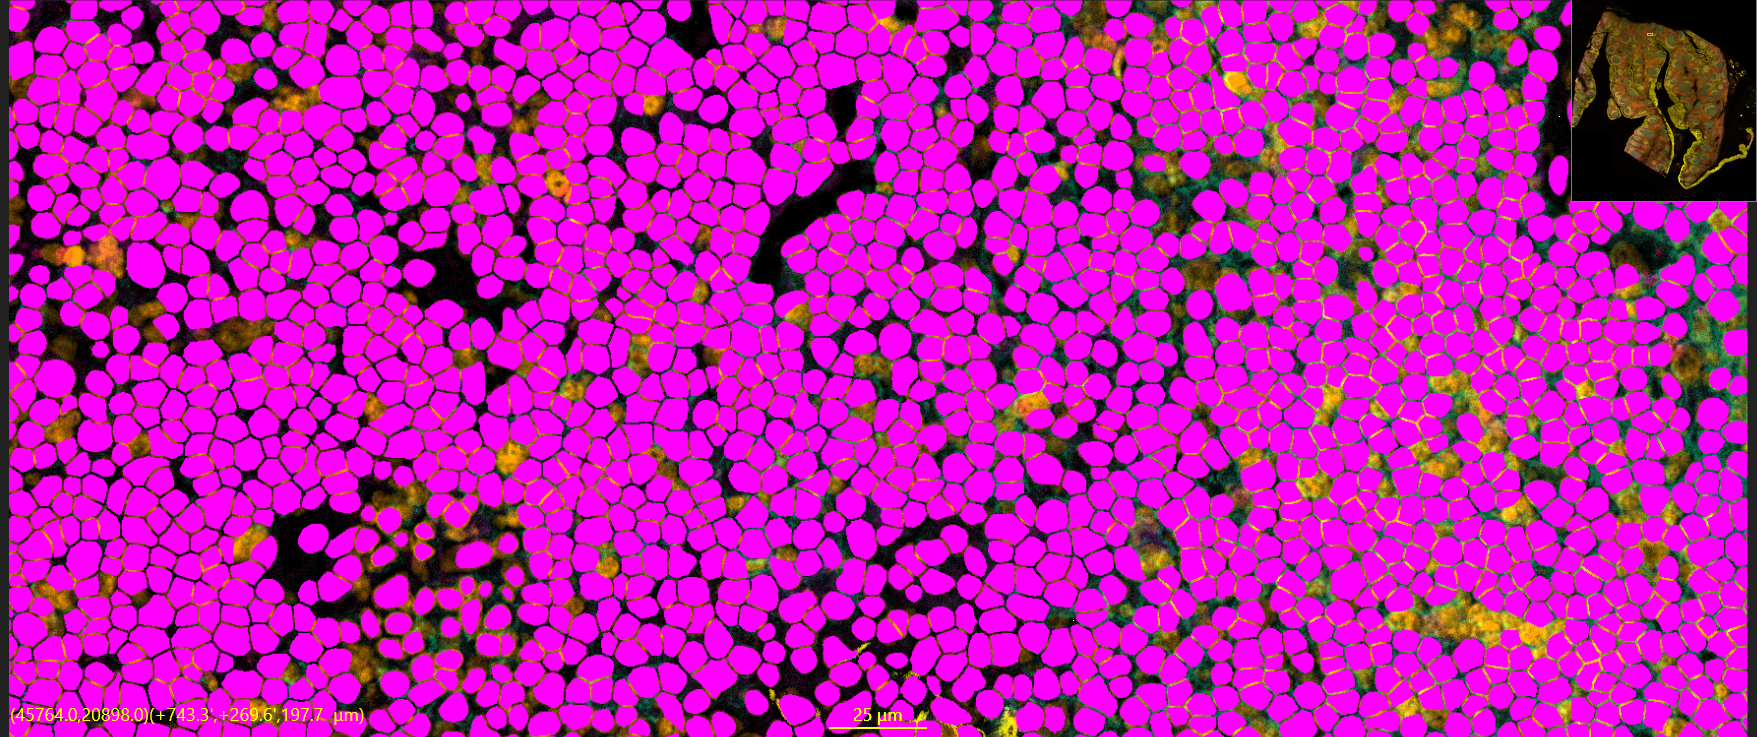

AI ANALYSIS:

Reproducible Accuracy

The COLUXA AEON CytoScanner system is a high-throughput laser scanning full spectral fluorescence microscope designed for imaging cells and tissue samples

4x, 10x, 20x, 40x, 60x

5 mins (1 cm^2 at 20x mag), Single Pass All Channels